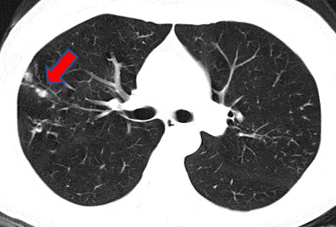

陈小姐咳嗽、咳痰的老毛病已经三年多了,断断续续用了很多药也不见好,最近的胸部CT说又发现了新的结节。陈小姐钻研了各路“就医宝典”,最终决定到中山感染病科看看。

医生给陈小姐安排了抽血检查,发现她的炎症指标中度升高,再结合她的病程胸部CT表现,考虑慢性低毒力的病原体引起的肺部感染可能大。有了大致的方向,医生给陈小姐安排了支气管镜检查。取到的标本做了微生物检测,包括传统的培养检查和新兴的基因检测,检出了少见的“盖尔森基兴诺卡菌”,完美证实了医生的推测。经过一系列抗感染治疗,陈小姐随访胸部CT左下肺病灶逐步吸收。

医生说,诺卡菌是一种毒性不是很强的病原体,感染之后一般不会导致高烧、剧烈咳嗽等等急性症状,而是多呈慢性病程。由于有效的药物与一般细菌不同,诺卡菌感染的重点和难点在于诊断,一经诊断,有针对性特效药治疗一般都可以取得良好的效果。